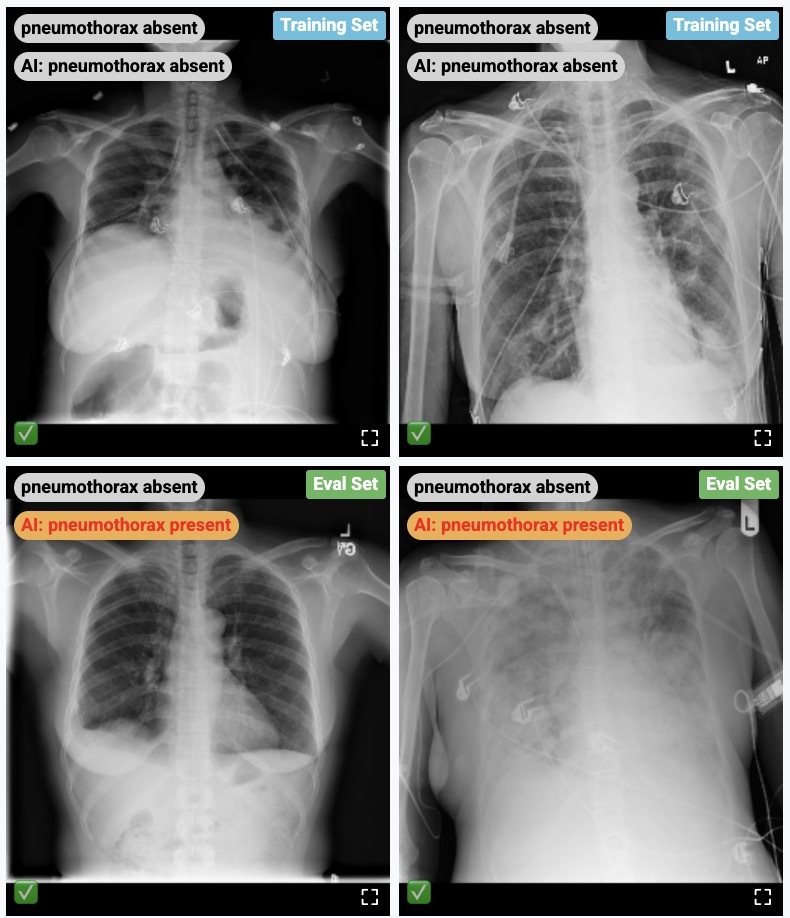

Demo usage of the CXR Foundation model embeddings